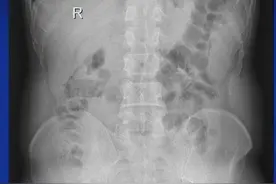

说到憋尿这事儿相信大家都经历过很多人都觉得憋尿顶多就是难受一会儿其实,它对身体的危害远超你的想象近日,河北省胸科医院泌尿外科就接诊了一位因为憋尿导致膀胱破裂的患者男子喝啤酒后去打篮球憋尿致膀胱破裂近日,王先生(化名)因肚子疼前去河北省胸科医院就诊。